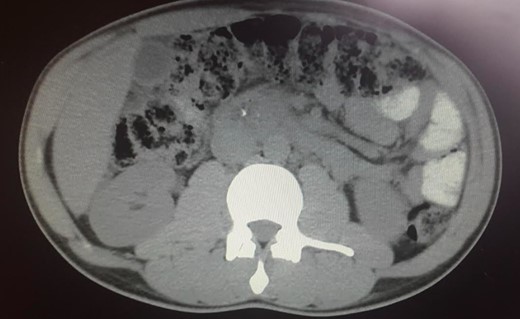

Laboratory tests including IgG4, anti-smooth muscle antibody (ASMA), anti-mitochondrial antibody (AMA), anti-nuclear antibody (ANA), anti-neutrophil cytoplasmic antibody (ANCA), anti-Sjogren’s-syndrome-related antigen A/B, anti-Smith (anti-Sm), anti-dsDNA, complement C3/C4, CEA and CA 19-9 were all negative. Endoscopic ultrasound (EUS) revealed a heterogeneous parenchyma of the pancreatic head and an EUS-FNA was performed. The MRCP, on the other hand, suggested the existence of a distal cholangiocarcinoma, because of the sudden typical stenosis in the distal CBD with a general dilatation of the upper bile ducts (Fig. 3). Unfortunately, the biopsy was not enough to establish a definitive diagnosis.

ERCP. Heterogeneous pancreatic parenchyma and pseudonodular appearance of the pancreatic head. Wirsung duct with no stenosis or obstructions. Common bile duct with normal caliber until the intrapancreatic portion where a highly suspicious of malignancy 2 cm irregular stenosis is seen.